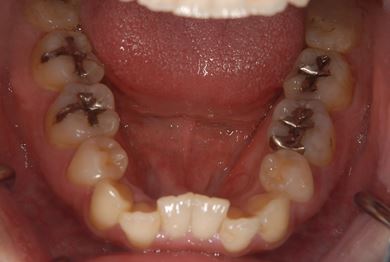

治療前

• 治療前